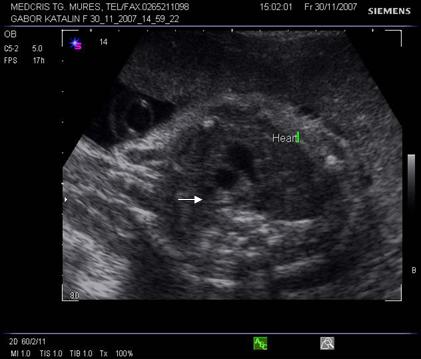

Fig. nr.177. Planul 1 de sectiune, cu imaginea de inima in 4 camere.

Evaluarea structurilor specifice in sectiunea 4 camere

Aorta apare la stanga coloanei

Atriul stang - valva de la foramen ovale (septum primum) floteaza ritmic in acest atriu. Venele pulmonare se dechid in atriul stang, iar acesta in ventriculul stang, spre apexul cardiac.

Ventriculul stang are forma ovalara, cu lumenul extins spre apexul cardiac, nu are trabecule tipice in miocard si valva mitrala este mai jos inserata fata de tricuspida (mai spre apex).

Atriul drept comunica prin foramen ovale cu atriul stang. Nu contine valva de la foramen ovale si apare mai mare decat atriul stang. Inferior de atriul drept si aproape de septul interatrial, apare terminarea venei cave inferioare cu valva lui Eustachio, ce are imagine de vas rotund. Atriul drept se deschide spre ventriculul drept.

Ventriculul drept - forma relativ rotunda si se distinge de cel stang prin 5 caractere:

cel mai aproape situat fata de stern

contine trabecule proeminente

lumenul nu se extinde catre apexul cardiac

valva tricuspida situata mai sus fata de mitrala (insertie la nivel diferit)

banda moderatoare - muschiul papilar, evident intre apex cardiac si tricuspida, in special intr-o sectiune laterala cu valva atrioventriculara inchisa.

Septul ventricular - apare ca o sageata de 2-4 mm, continuu.

Septul atrial - central intrerupt de foramen ovale, cu o valva batanta

Venele pulmonare - cele drepte se pot evidentia la intrare in atriul stang

Pericardul apare ca o margine, fina anecogena, normala